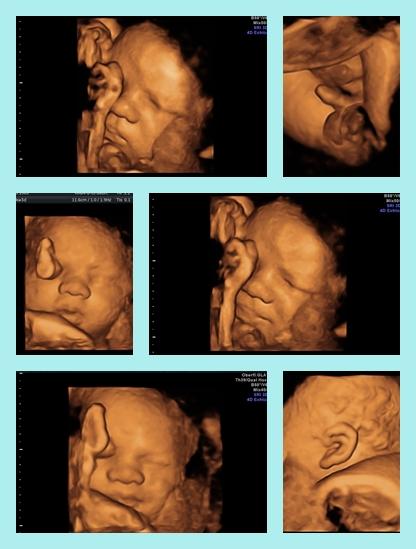

guck mal, meine 3d Bilder aus der 38. ssw :-D von wegen das geht später nicht auch gut :-D Also einfach mal weiter hoffen. ich wollte die 3d Bilder gar nie machen lassen aber die vertretungsärztin hatte einfach welche gemacht und ich war dann hin und weg.... kann deine Vorfreude voll verstehen. hätte ich vorher nicht gekonnt ;-)

hm neee habe eine collage angehangen. kannst du sie nicht sehen oder nicht öffnen?

Ohh die sind ja klasse, sehr schicker Junger Mann...